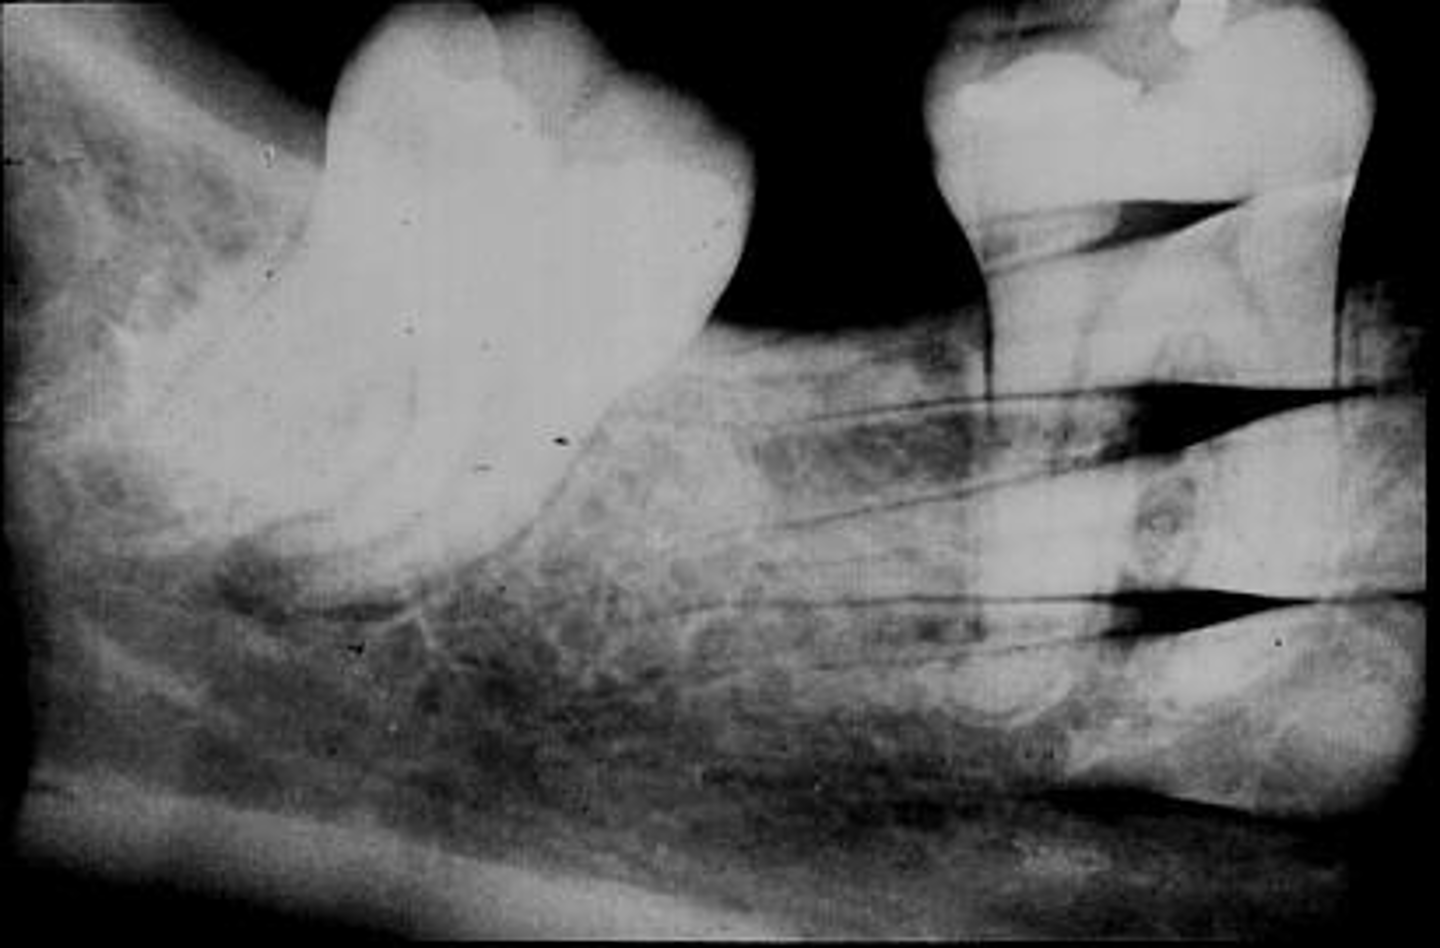

What is this error?

Damage, elongation, can't see apices